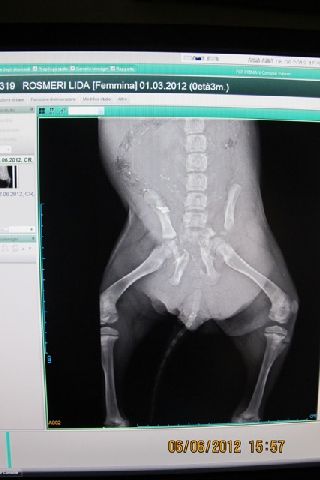

Guardate in che condizioni questa piccina ha il bacino?

Se la situazione migliora la piccola potrà essere sottoposta ad un delicatissimo intervento ortopedico al bacino.

Stabilizzata è stata sottoposta a radiografie le quali hanno evidenziato micro fratture al bacino ed al sacro con problemi alla vescica.

Ricordo che Maddie, condotta a visita a seguito di trauma da investimento presentava deficit deambulatorio legata a una serie di fratture del bacino fra le quali un distacco delle diastasi sacro iliache. Un anemia gravissima per la quale e'stato necessaria procedere con una trasfusione nelle ore successive al ricovero.